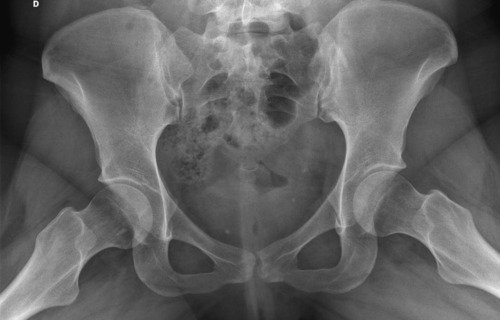

Não sei por onde começar porque e uma história longa e vou tentar resumir, fiquei meses tentando descobrir que eu tinha fibromialgia, porém eu não tenho só isso, tive edemas na coluna, problemas na lombar, e até derrame pleural eu tive, eu pago aluguel que e 1300 mais o condominio que e 450, fora que eu me planejei e não tenho familia pra apoiar entre outras coisas, quando me mudei e planejei pra poder ter o proprio ape eu não sabia que do nada iria ficar doente, em março de 2023 eu pego as chaves mas até la ta dificil, fiz emprestimo e várias outras coisas porque só a medicação de durogesic que eu uso e restiva um a caixa e 650 e o outro 300, podem pesquisar, após um procedimento na lombar cirurgico pra tentar aliviar a dor descobri uma necrose asseptica na cabeça dos dois femur, com risco de ter que colocar uma protese, até pouco tempo estava de muleta, só podia ficar sentada, e mesmo a dor e muito forte, eu ainda não sei a tal outra doença que eu tenho, já aconteceu de eu entrar na emergência e ficar na UTI, tive mais de 10 internações no hospital e não e mentira, minha maior luta e conseguir tratar essa necrose, poder voltar a praticar esportes, sei que tem gente que precisa muito mais mas eu cheguei no meu limite e to até com um aluguel atrasado, todas as coisas que eu estiver pagando eu vou colocar nota fiscal porque eu não to aqui pra fazer ninguém de trouxa, vou colocar exame, fotos de internação entre outras coisas que posso, porque tem algumas que não posso devido porque não quero imagem negativa para local de trabalho (e aonde eu trabalho eles estão me ajudando e muito), e de acordo de como for funcionando a vakinha eu vou vendo se aumento, eu só queria me livrar dessas contas sufocantes primeiro, e agora os médicos estão lutando pra descobrir a outra doença que tenho além dessa da necrose que ta me deixando muito mal e que a fibromialgia atrapalha a descobrir, sei que e chato porque já pedi ajuda 2 vezes, mas conversei com amigos e infelizmente eu não tenho outra opção a não ser pedir ajuda, vou colocar exame de tudo etc, o valor até de emprestimos que estou devendo e tudo mais, e podem me perguntar qualquer coisa que eu respondo e claro, vou postar nota fiscal pra provar que to pagando o que to mostrando, eu to no meu limite, e não e fácil, eu ficava 3 dias seguidos sem conseguir dormir e os médicos não conseguiam descobrir e ainda sigo firme no tratamento porque vou encontrar uma resposta e não posso desistir do tratamento, eu poderia fazer um textao aqui mas com poucas palavras já consigo ser direta, obrigada a quem ajuda e continua me apoiando desde o começo e pra quem não gosta e não acredita e só não ajudar, ninguém vai ficar inventando internações etc pra ficar ai pedindo dinheiro de graça pra ostentar, não gosta só não infernizar, só cada um sabe o sofrimento que ta passando na própria pele e a sua luta diária, agradeço se puder ajudar, aceito tudo que seja positivo e desejo o dobro de bom pra cada um.